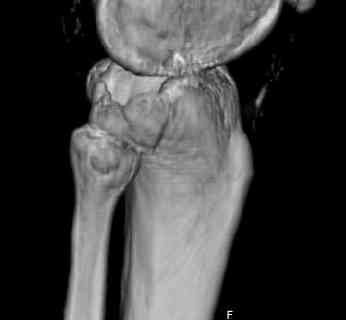

Здравствуйте, уважаемые коллеги!Подскажите, пожалуйста, какой выбрать доступ и способ фиксации при импрессионном переломе заднего отдела наружного мыщелка большеберцовой кости. Женщина 40 лет, травму получила 02.01.2008, катаясь на горных лыжах.Есть ли здесь необходимость использовать задний доступ, или можно справиться через наружный? Есть ли шансы сделать закрыто - под ЭОП через медиальное "окошко" поднять забойником суставную поврехность? Какой лучше использовать фиксатор?Спасибо.

In this situation, where the fragment is posterolateral, one needs a posterior approach, either as described by Timothy Bhatacharya et al in 2005 in JOT, which involves taking down the medial head of the gastrocnemius, or the Lobenhoffer paper which involves a transfibular approach.

would anyone consider an anterolateral approach with a sagital osteotomy just lateral to midline?

this would give access to the impacted posterior region. then "backgraft", and fix the osteotomy

fragment with a standard anterolateral plate. thanks.